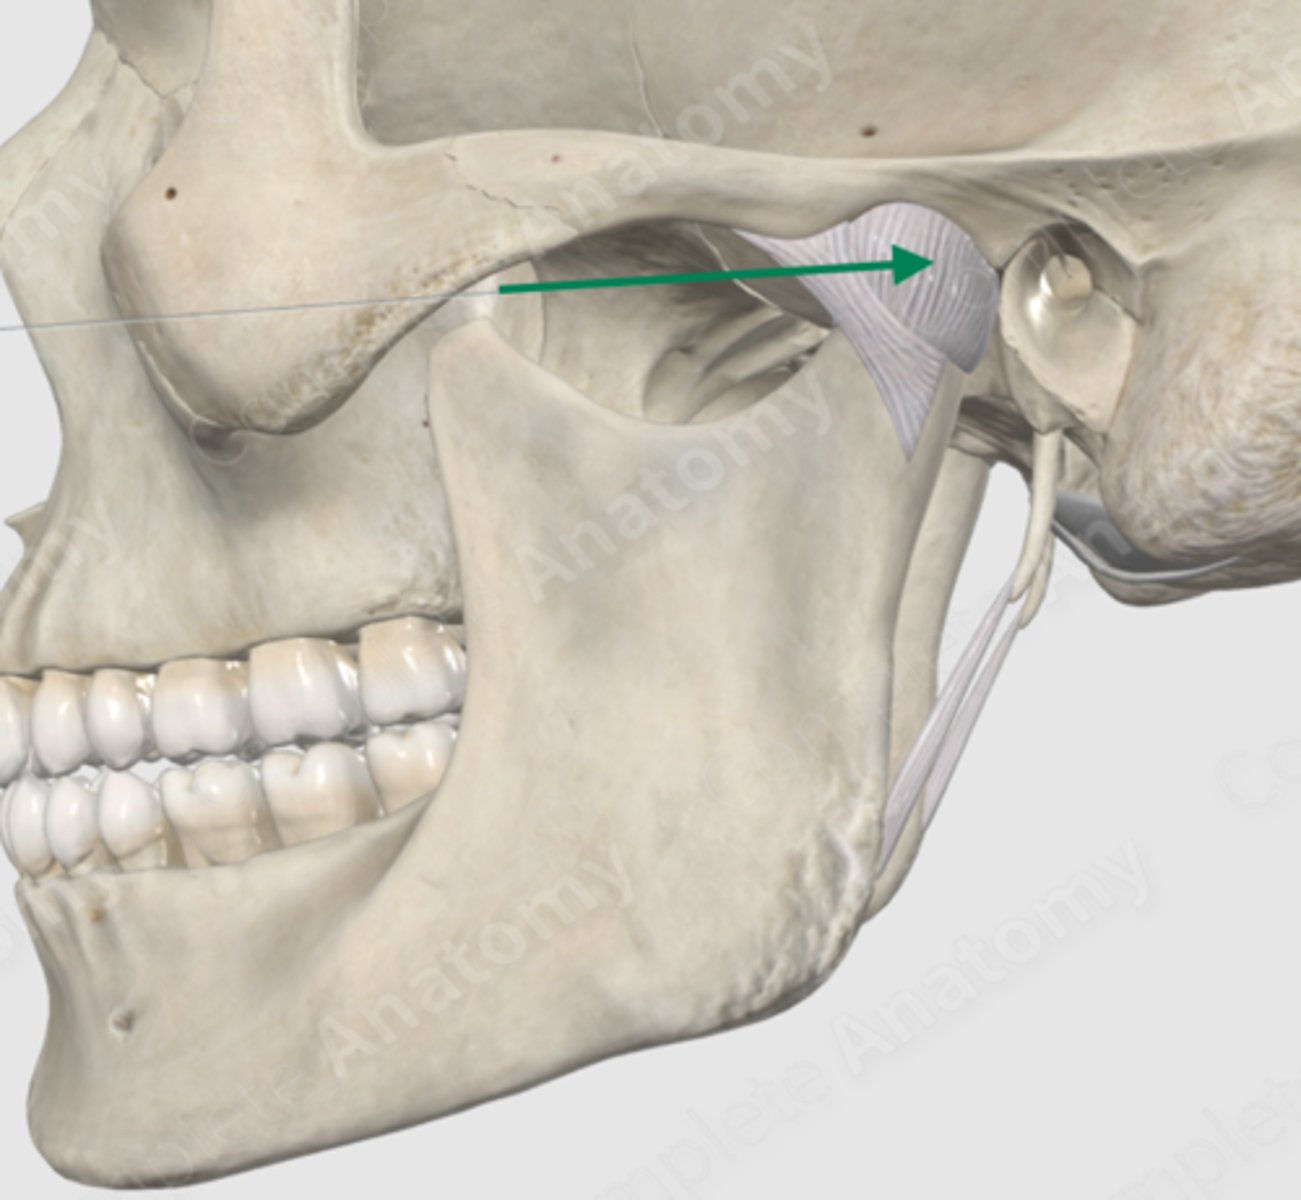

temporomandibular joint capsule

lateral pterygoid

lateral pterygoid, superior part

lateral pterygoid, inferior part

articular tubercle

head of mandible

articular disk

joint capsule